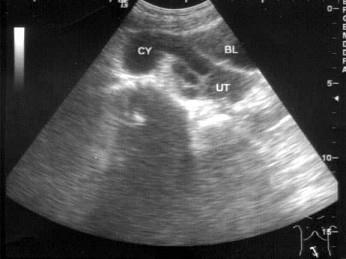

问题 女,27岁,下腹部疼痛数月,体检:右侧附件区增厚、增大,B超检查如图所示,最可能的诊断为?(?)

选项 A.右侧卵巢囊肿 B.右侧输尿管扩张 C.右侧输卵管积液 D.盆腔积液 E.以上都不是

答案 C